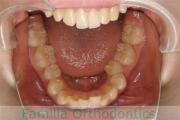

No.22V-449

- 主な症状:

- 上顎前突

- その他の症状:

- 叢生

- 年齢:

- 14歳

- 性別:

- 男性

- 抜歯部位

- 上:

- 44

- 下:

- 8448

- 主な使用装置:

- FEA

- 治療にかかった費用:

- 87万円

歯並びをきれいにしたいということで来院されました。上下左右から小臼歯を抜歯して、マルチブラケット法を行っています。2年弱、25回程度の通院が必要でした。

かなり強い叢生(でこぼこ、凹凸、ガタガタ)ですので、保定をしっかりしないと後戻りのリスクがあります。

- ≫治療前

-

上顎

下顎

前歯の関係など

右側

正面

左側

- ≫治療後